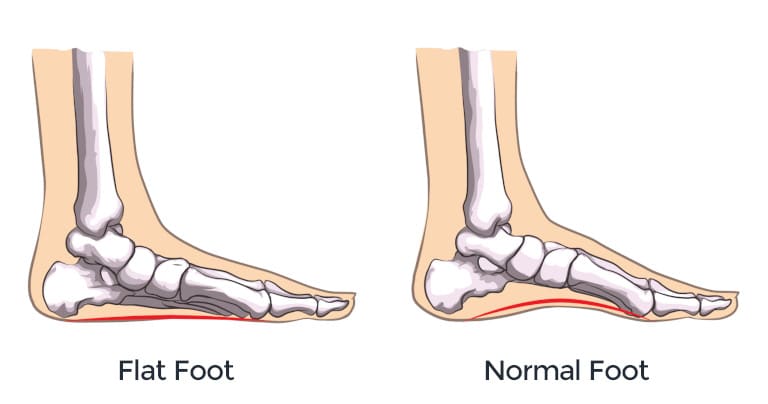

في الالتواء الأول، قد تتمدد الأربطة أو تتمزق. هذه الأربطة هي المسؤولة عن تثبيت الكاحل.

إذا لم تلتئم بشكل كامل، أو لم يستعد الكاحل قوته وتوازنه عبر التأهيل، يبقى المفصل أضعف من الطبيعي.

وهنا تبدأ المشكلة: الكاحل يصبح أكثر عرضة للألم، وأكثر قابلية للالتواء مرة أخرى.

السبب الأكثر شيوعًا هو بقاء الأربطة في حالة ضعف أو ارتخاء بعد الإصابة.

- صورة أوضح من عدم الاستقرار المزمن